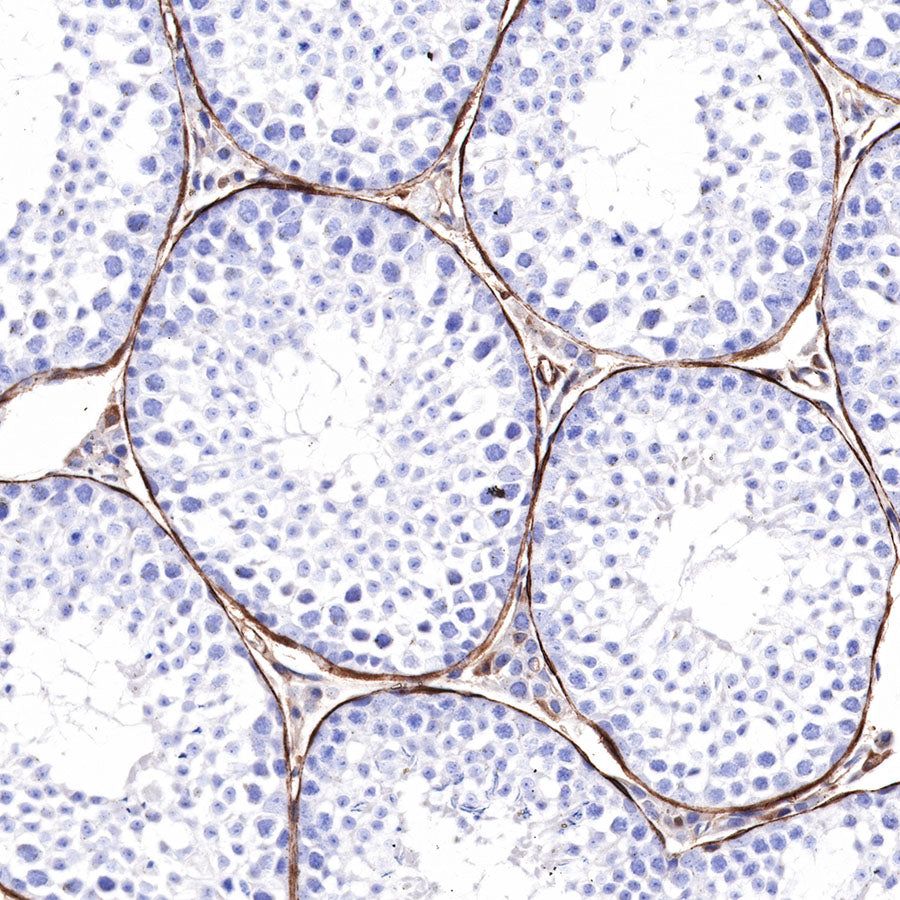

Immunohistochemistry